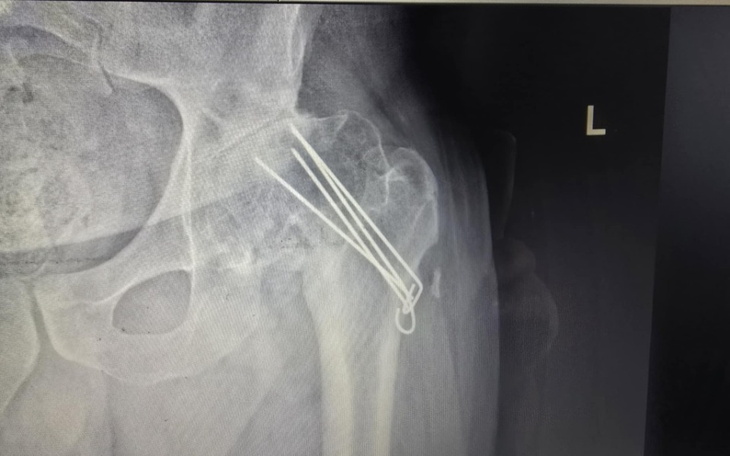

Ruszamy ze zbiórka dla człowieka, który wielokrotnie na grupie " Pomaganie przez licytowanie - Gang Pomagaczy" nie wahał się by pomóc innym. Odkąd działa grupa pomagaczy, sam podarowywal swoje uslugi i grał charytatywnie dla ludzi, którzy potrzebowali pomocy. Teraz on sam potrzebuje NASZEJ pomocy. Robert Zoch, bohater tej zbiórki od urodzenia zmagał się w wada biodra. W 1997r miał pierwsza operacje, gdzie w trakcie zostały założone mu druty, które miały polepszyć stan biodra i nogi. W 2004 roku odbyła się następną operacja, usunięcia drutów. Jak się później okazuje z winy lekarza , oraz błędu lekarskiego druty nie zostały usunięte. Roberta czeka operacja , a później długa rehabilitacja. I tu razem możemy pomóc przyspieszyć działania lekarzy, żeby Robert nie odczuwał bólu i mógł poruszać się bez problemu.